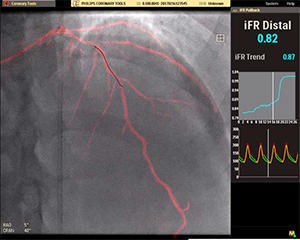

Courtesy from Dr. Eric Van Belle CHRU de

iFR*3の値とプルバックカーブをリアルタイムで自動表示し ,心臓冠動脈疾患の低侵襲性治療を積極的に支援する。

2. 血管画像とiFR値の比較レビュー

同一画面で比較レビューができるため,計測後の治療戦略が立てやすくなる。